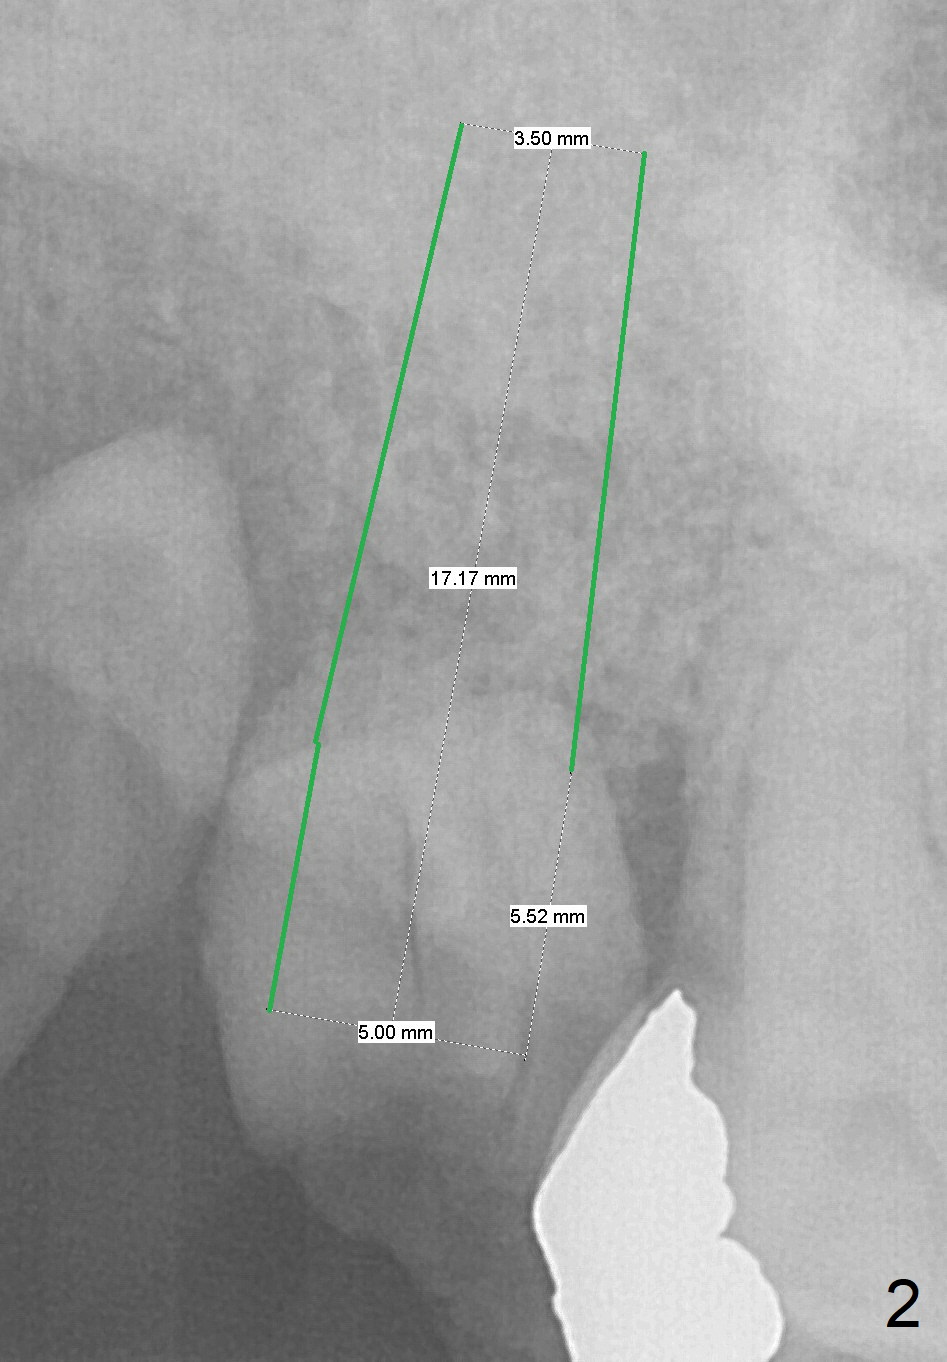

A 60-year-old woman requests extraction of the upper right 2nd and third molars and one implant (Fig.1). Although there is no problem of bone height, the intermaxillary vertical space is limited (data not shown). After implant (Fig.2) and abutment placement, the opposing tooth may need heavy reduction. Pay attention to implant trajectory so that a straight abutment will be used to avoid restorative complication (screw loosening).